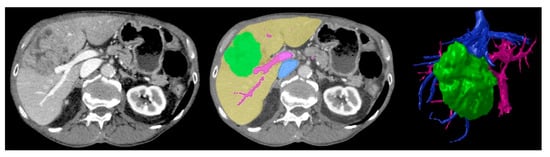

Traditionally, LCR surgical planning is based on a patient’s CT and/or MRI imaging. The surgeon uses 2D axial/multiplanar images and 3DVRs to determine appropriate resection planes and vascular/biliary reconstruction approaches. This requires using images on a 2D screen to construct a 3D mental visualisation of sophisticated patient liver structures. 3DPLMs can facilitate this task by providing a transparent [13,14,15,16,17,22,31], colour-coded [12,15,16,19,22,32,34,35,36,40], tactile [11,14,15,16,40], manipulable [11,14,16,19,29,31,40] and highly cognisable [14,15,16,17,19,29,31] representation of individualised patient liver anatomy, which improves comprehension of the complex and highly variable 3D spatial relationships between intrahepatic structures [14,16,19,22,29,31,33,40] and enhances cognitive localisation of liver tumours [15,16,17,29], as demonstrated in Figure 2. The improved anatomical perception assists surgeons in selecting the most appropriate surgical strategies [11,14,16,17,19,29,33,40], resection planes [13,16,17,33,40], and vascular reconstruction approaches [13,40].

Figure 5. Baseline CT image (left) vs. segmented image (middle) where green = tumour, yellow = liver parenchyma, pink = arterial vasculature, blue = venous vasculature, vs. final STL 3D rendering (right) demonstrating corresponding anatomical structures. Reproduced with permission under the open access from Witowski et al. [17].